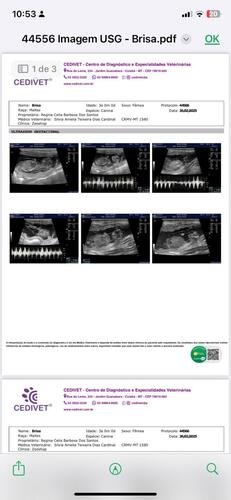

A briza, uma cachorrinha muito querida e carinhosa, de apenas 4 anos,foi encontrada na beira de uma estrada, com risco de atropelamento. Então resgatei ela e percebi que estava com muitos carrapatos, corri com ela para o veterinário para fazer exames. Os resultados dos exames acusaram uma infecção nela, precisou fazer uma ultrassom para localizar a fonte da infecção e assim foi notado que ela estava gestante de 6 filhotes, e três já estavam mortos. E se nada fosse feito os outros cachorrinhos poderiam morrer e até mesmo ela. Foi necessário uma cirurgia de emergência. Na tentativa de tirar os filhotes com vida, infelizmente não resistiram.